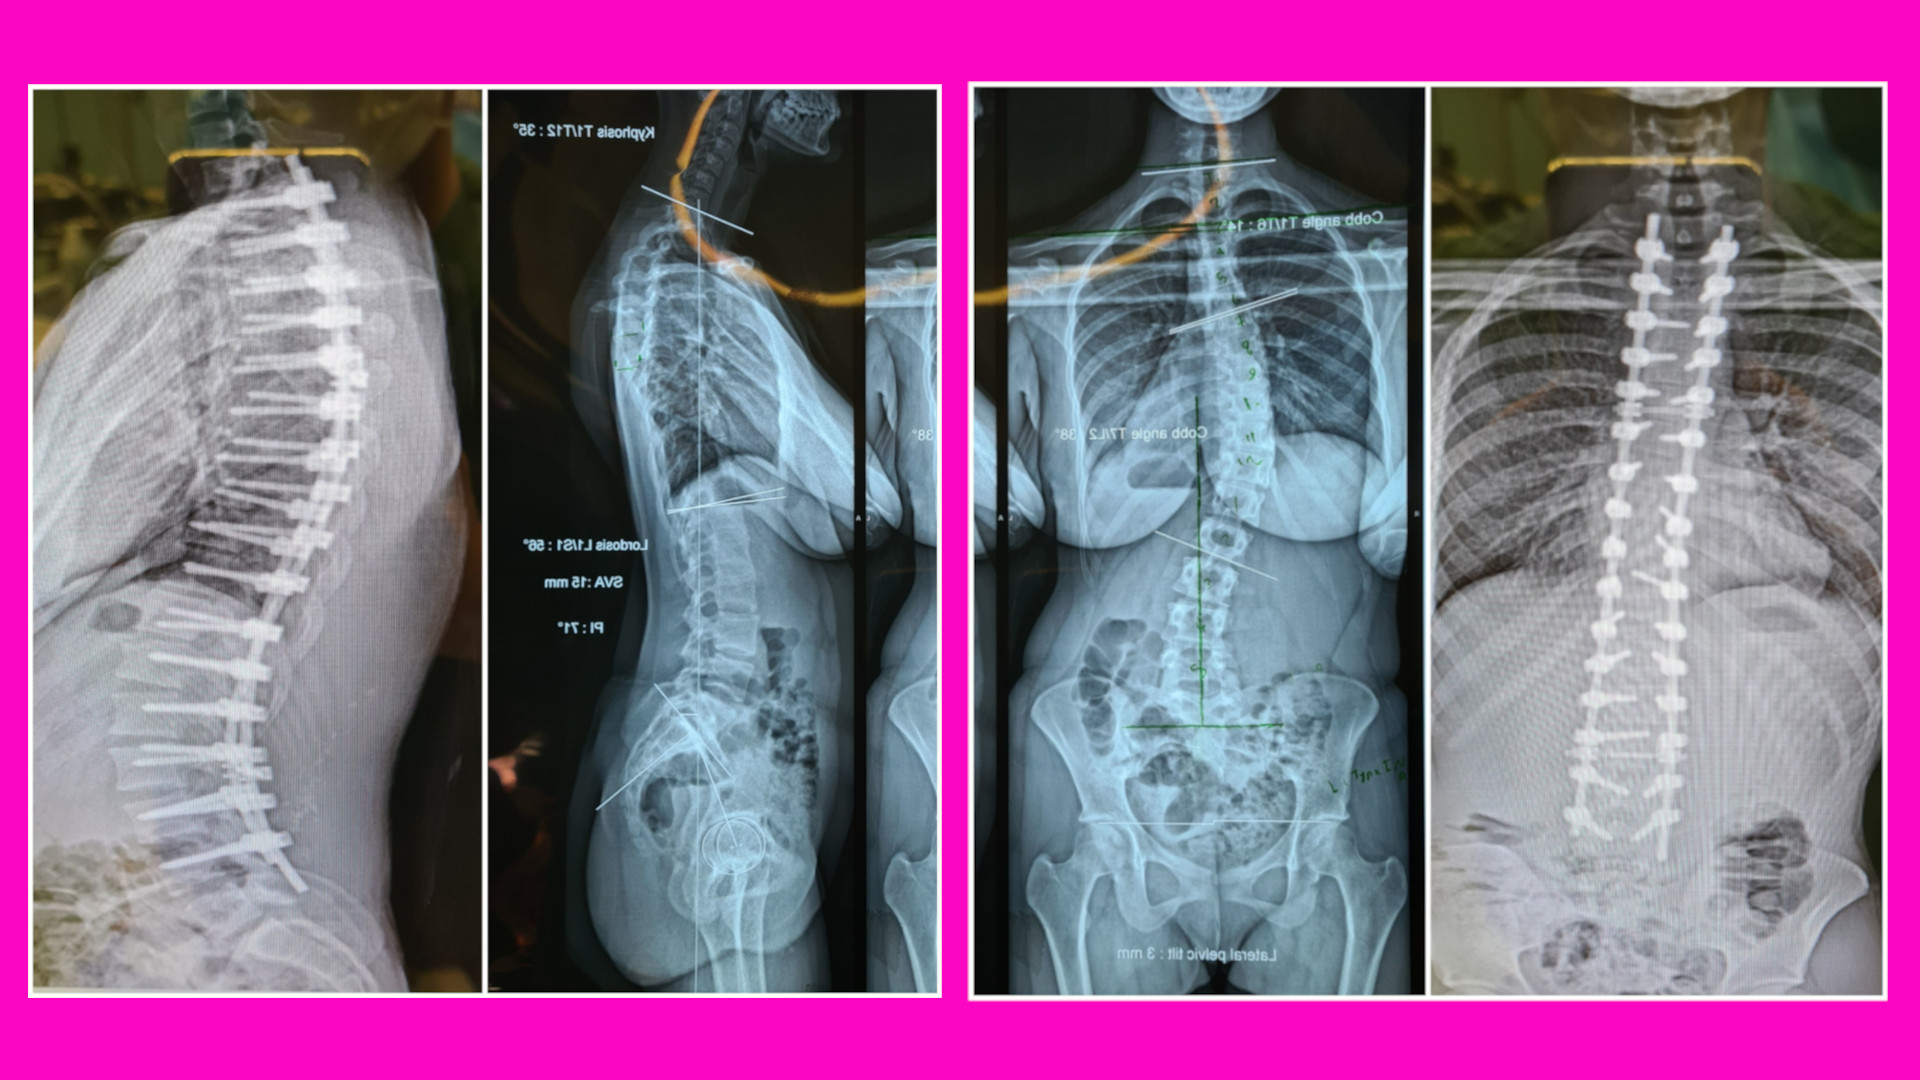

شکل بالا ستون فقرات یک دختر ۱۵ ساله را نشان می دهد که دچار یک بیماری به نام اسکولیوزیس است. در این بیماری که معمولاً در سنین نوجوانی رخ می دهد ستون فقرات شروع به خم شدن میکند. معمولاً علت آن ناشناخته است. اگر زاویه این خمیدگی بیشتر از ۵۰ درجه باشد یا خمیدگی به طور سریع در حال پیشرفت باشد بیمار نیاز به عمل جراحی دارد. برای تصحیح قوس کمر این بیمار، از پشت برش انجام شده و از مهره دوم پشتی تا مهره چهارم کمری پیچ گذاری انجام شده سپس پیچ ها با یک میله بلند بنام rod که طبق اصول خاصی خمیده شده است به هم متصل شده اند تا بیمار قوس طبیعی کمر خود را به دست آورد. دو عکس وسط عکس بیمار را قبل از عمل جراحی و دوعکس جانبی عکس بیمار را بعد از پیچ گذاری و تصحیح ستون فقرات به شما نشان می دهد.